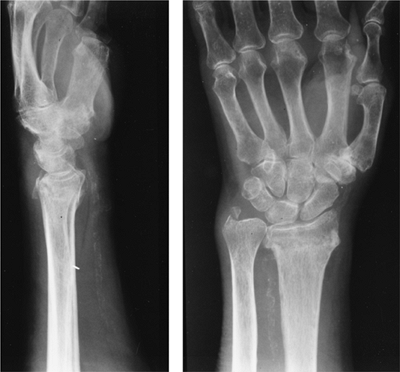

![]() |

FIGURE 9-2

Lateral and PA radiographs of the wrist showing a typical Colles fracture with dorsal impaction of the radius and an ulnar styloid fracture. The fracture extends into the DRUJ (Type B). |